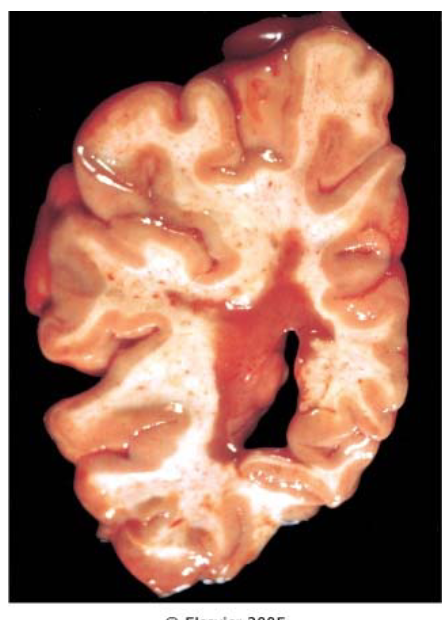

What pathology is shown in the provided image?

MS

wel circumscribed, tan, irregularly shaped plaque in periventricular white matter (demyelinating)